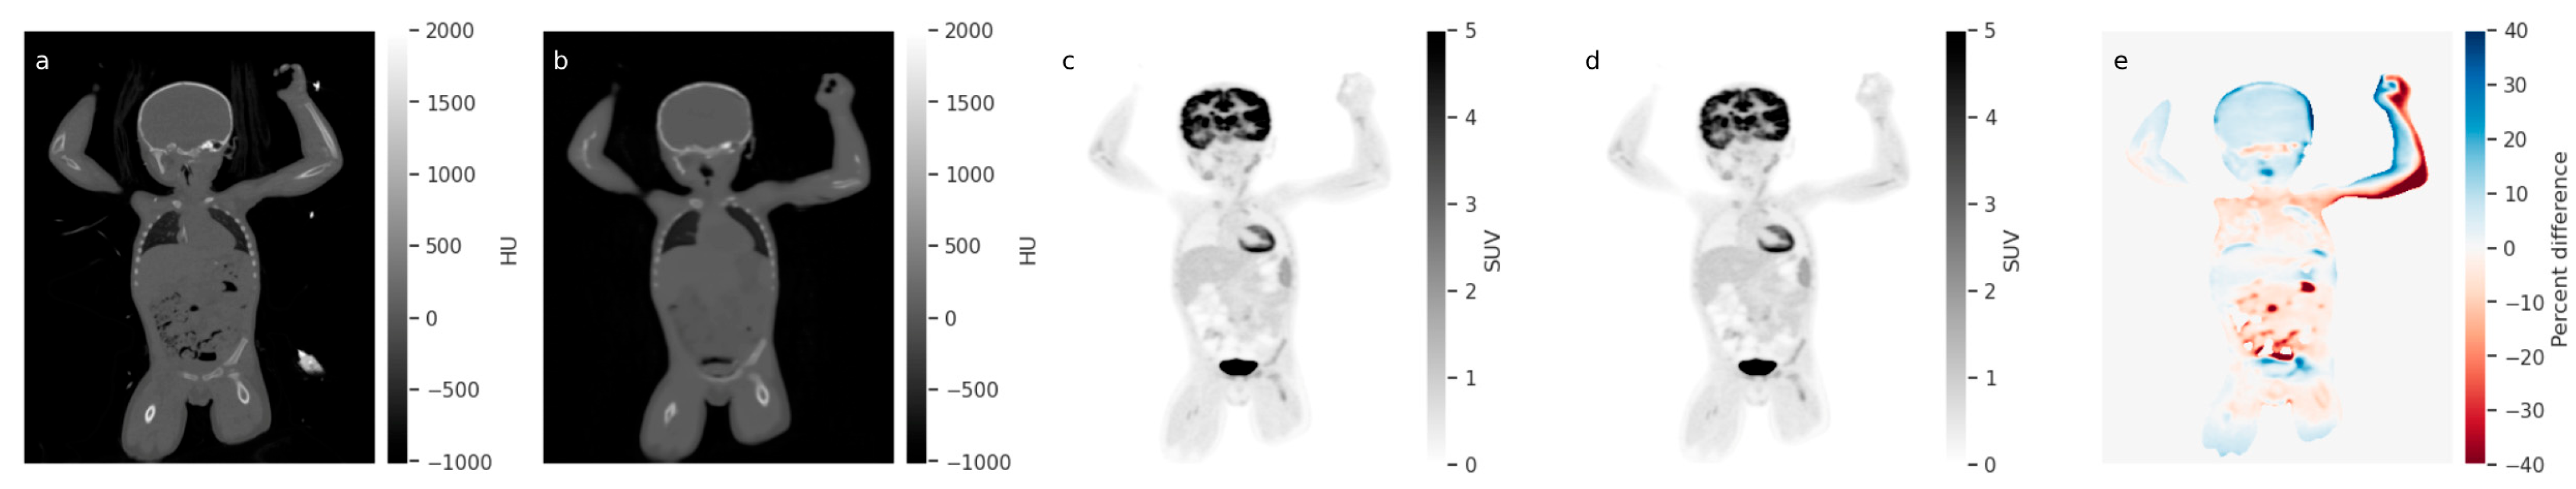

- Montgomery, M.E.; Andersen, F.L.; d’Este, S.H.; Overbeck, N.; Cramon, P.K.; Law, I.; Fischer, B.M.; Ladefoged, C.N. Attenuation Correction of Long Axial Field-of-View Positron Emission Tomography Using Synthetic Computed Tomography Derived from the Emission Data: Application to Low-Count Studies and Multiple Tracers. Diagnostics 2023, 13, 3661. [Google Scholar] [CrossRef]